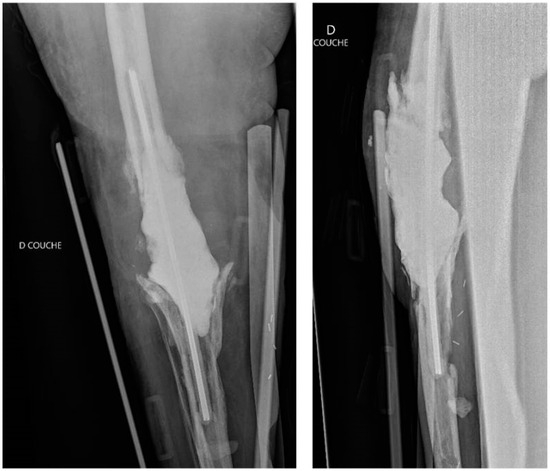

Spacers may contain multiple antibiotics [5,11]. When the causative bacteria are identified and sensitive to a specific antibiotic, using a single agent may be sufficient [11]. However, when the bacteria are unknown, it is preferable to combine antimicrobials to cover a broader spectrum, including both Gram-positive and Gram-negative bacteria [5,11]. The antibiotics most commonly used for cement impregnation are tobramycin, gentamicin, vancomycin, and cephalosporins [5]. Vancomycin is effective against MRSA, gentamicin targets Enterobacteriaceae and Pseudomonas aeruginosa, and cefotaxime is effective against gentamicin-resistant bacteria [5]. A popular combination is an aminoglycoside (tobramycin or gentamicin) with vancomycin [11,18,26] (Figure 1).

Figure 1.

An example of a hand-made static antibiotic-loaded cemented spacer in a case of severe periprosthetic joint infection. Anteroposterior and lateral post-operative radiographic views of the right knee after removal of the infected implants and placement of a cemented spacer loaded with vancomycin and gentamycin, fixed with two metal rods [50]. [Authors’ previously published work, used under the terms and conditions of the Creative Commons Attribution (CC BY) license (https://creativecommons.org/licenses/by/4.0/, accessed on 10 August 2024).].